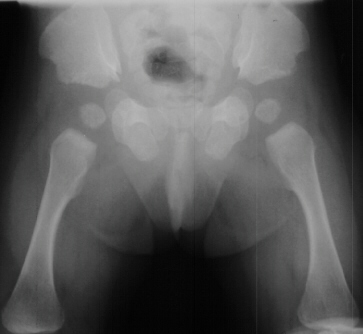

RADIOGRAPHS:

Plain x-ray's showed a sixth metacarpal and phalanx on the ulnar border

of both hands

.

The distal phalanges are shortened relative to the proximal and distal

segments. The pelvis

has

small, squared iliac crests with spikes of bone at the triradiate cartilages.

The tibial segments

are

disproportionately shorter than the femoral segments.

- Characteristic features of the pelvis includes:

- small iliac crests and sciatic notches

- originating from the triradiate cartilage a distally directed spike